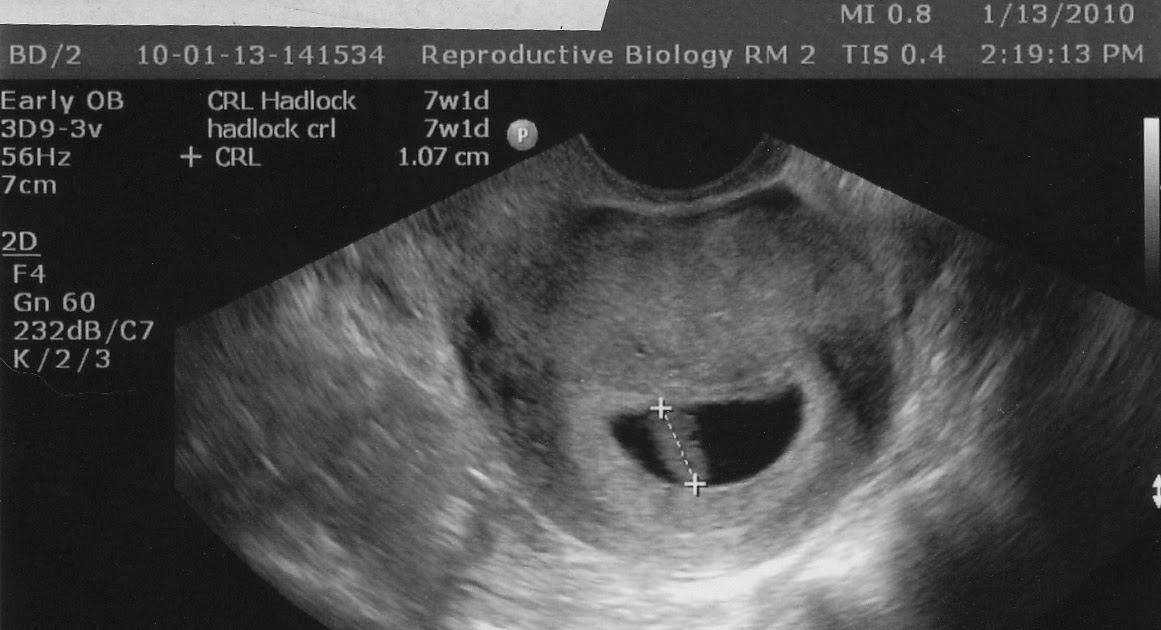

Non viable early pregnancy, missed abortion, large yolk sac, ultrasound

Non viable early pregnancy, missed abortion, large yolk sac, ultrasound What Is An Enlarged Yolk Sac After a pregnancy test comes back positive, an ultrasound done around six weeks after your last period can provide the next clue as to how everything’s progressing in there. Despite its minuscule size, the yolk sac relays an important visual message on an ultrasound — and fuels a growing embryo's nutrient needs. The yolk sac (ys) is the primary source. What Is An Enlarged Yolk Sac.